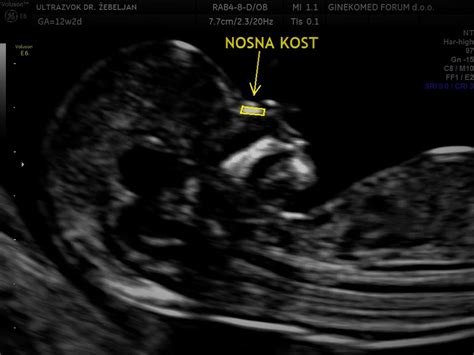

Meritev nuhalne svetline, kot pojasnjuje ginekolog in porodničar dr. Stanko Pušenjak, je poenostavljeno poimenovanje za sklop ultrazvočnih preiskav. Gre za celovit presejalni test, s katerim se preverita trajanje nosečnosti in anatomija ploda, kolikor je to mogoče v tem zgodnjem obdobju. Na podlagi meritve nuhalne svetline, preverjanja prisotnosti nosne kosti ter analiziranja drugih morebitnih značilnosti, kot so oblika obraza ali pretoki skozi srčne zaklopke in venske duktuse, lahko ginekolog napove tveganje za kromosomske napake, predvsem za Downov sindrom.